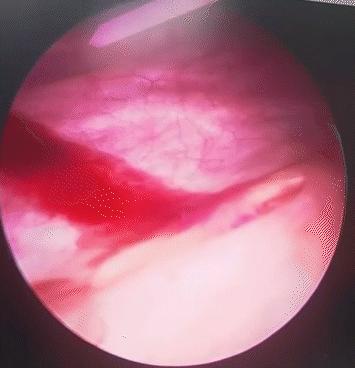

输尿管口间断性喷射血尿

手中,在膀胱镜下清晰可见左侧输尿管口间断性喷射血尿,这更加坚定了之前上尿路出血的推断,在高清软镜支持下,在左侧肾盂部见到了导致周女士长期血尿的“罪魁祸首”——一块灰白色的絮状物,随即对该絮状物送病理检查。